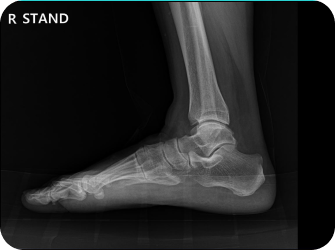

척추 엑스레이 검사

족부 엑스레이 검사

다리길이 엑스레이 검사